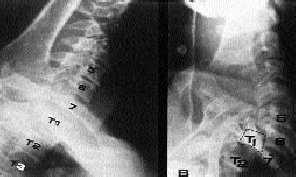

El riesgo de errar el diagnóstico en estas graves lesiones deriva principalmente de un estudio radiológico incorrecto. Las proyecciones necesarias son las habituales, A-P y lateral de columna cervical.

Ante un paciente con un traumatismo relevante (no digamos ya si se trata de un politraumatizado) y dolor cervical es imprescindible que la radiografía lateral de columna cervical muestre desde el occipucio hasta la primera vértebra dorsal. La dificultad para obtener una radiografía lateral en la que se vea la última vértebra cervical es la principal causa de omitir el diagnóstico de una lesión cervical. Cuando la imagen obtenida no cumpla estos requisitos deberá intentarse de nuevo, haciendo tracción longitudinal de cuello y tracción de las manos hacia abajo (incluso tras administrar diacepán por vía intravenosa). Si aun así no se consigue ver la charnela cervicodorsal, se puede intentar la «proyección del nadador» (fig. 17) con un brazo abducido 180 grados, el otro traccionado hacia abajo y pegado al cuerpo, y el tubo de rayos oblicuado 60 grados.

Fig. 17. Proyección del «nadador» en la fractura-luxación de la séptima vértebra cervical.